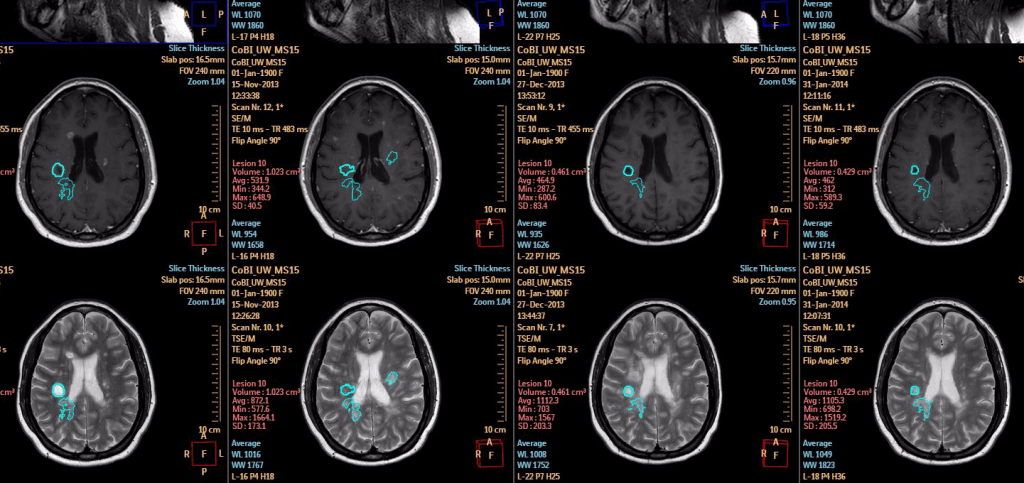

Een van de nieuwe oplossingen is een pakket softwareapplicaties voor neurologisch MRI-onderzoek. Ook komt Philips met een update van het IntelliSpace Portal, het dashboard waarmee radiologen naar medische beelden zoals CT-scans en röntgenfoto’s en relevante patiëntinformatie kunnen kijken. Nieuw bij deze versie van IntelliSpace is dat Philips machine learning capaciteiten inzet om de arts te ondersteunen. Het IntelliSpace Portal werd al gebruikt voor oncologie, cardiologie en radiologie, en wordt nu ook uitgebreid naar neurologie.

Prof. Dr. Mark van Buchem is radioloog en hoogleraar neuroradiologie in het Leids Universitair Medisch Centrum (LUMC). “Bij neuroradiologie is MRI onze grootste vriend. MRI is een techniek die enorm breed inzetbaar is en een schat aan structurele en fysiologische informatie over de hersenen kan blootleggen.” Neuroradiologen kijken met het blote oog naar de digitale MRI-beelden, en kunnen adequaat en snel een diagnose stellen en een verslag schrijven. Maar er zijn een paar beperkingen, volgens Van Buchem. De analyse van de neuroradioloog noemt hij een inschatting, een artist impression. “Een analyse met het blote oog is niet kwantitatief. Waar we ook heel slecht in zijn, is om subtiele veranderingen over tijd waar te nemen met het blote oog. Ook is het lastig om uitspraak te doen over bijvoorbeeld het onderscheid tussen het krimpen van hersenen als effect van leeftijd, of als gevolg van een aandoening als atrofie.”

Neuroradioloog Mark van Bruchem: "Subtiele veranderingen over tijd zijn erg lastig waar te nemen met het blote oog"

Van Buchem doet bij het LUMC onderzoek naar de hersenen. Hij noemt het systeem van Philips een doorbraak. “Ik gebruik al vijftien jaar digitale systemen voor het analyseren van beelden, maar dat is enkel voor onderzoek, niet voor de dagelijkse patiëntenzorg. Met deze nieuwe software en service heeft een radioloog een werkstation om beelden te kwantificeren, analyseren en veranderingen over tijd bij te houden, die past in de workflow.”

IntelliSpace vergroot volgens de neuroradioloog de accuraatheid van diagnoses. “Het systeem gaat bijvoorbeeld op zoek naar veranderingen tussen foto’s, visualisatie van veranderingen en afwijkingen. We turen ons een ongeluk, maar hiermee hebben we het direct in beeld.”